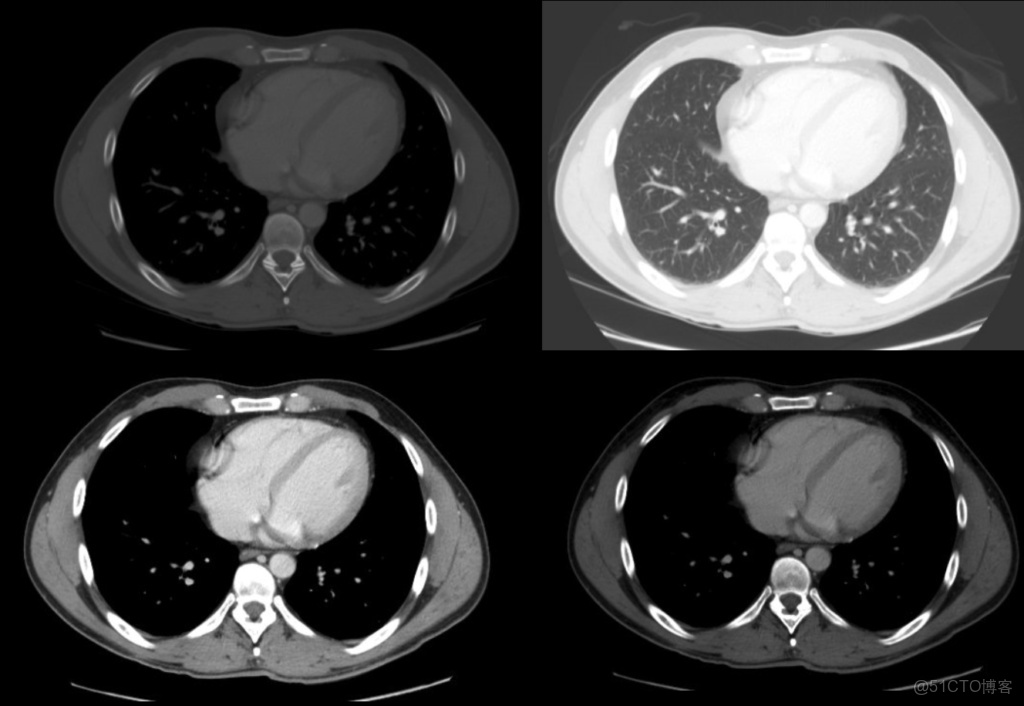

上圖顯示了不同的窗口設置,這些窗口設置展示了窗口化對CT掃描外觀的巨大影響。

這些窗口設置只是CT掃描的圖像處理功能,有助於突出顯示關鍵的解剖結構/發現,從而使圖像解釋儘可能容易。例如使用“骨骼窗口”清晰地顯示掃描的骨骼,以識別骨折。